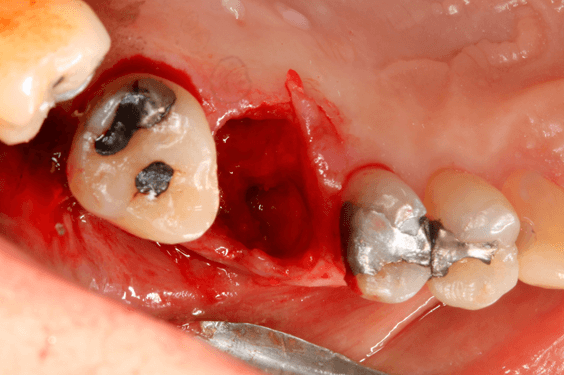

A preservação do alvéolo é uma opção de tratamento, evitando ou reduzindo a perda óssea. Alguns procedimentos são sugeridos com o objetivo de reduzir essa perda fisiológica, como a utilização de biomateriais preenchendo o alvéolo, barreiras, instalação de implante imediato entre outros. 4

Avaliamos o desempenho do biomaterial de hidroxiapatita com colágeno tipo I (Extra Graft XG-13®) na manutenção do volume alveolar.

A aplicação como o caso clínico abaixo se mostrou uma técnica acessível a todos cirurgiões dentistas, pois se trata de um procedimento de simples execução e acessível. Logo, deveria constar na clínica diária.